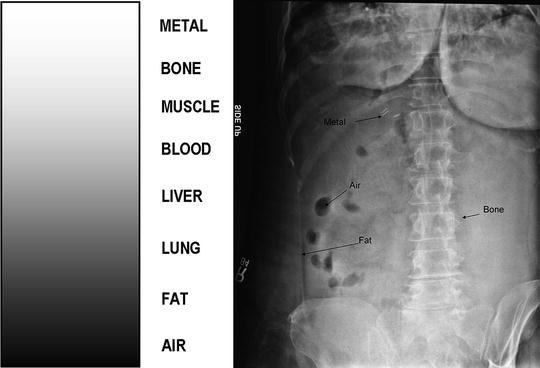

Radiographic Densities

The varying appearances of structures in radiographic imaging based on their density.

Air Density

The lowest density in radiographic imaging, appearing black on images.

Fat Density

A density level that appears darker than soft tissue on radiographs.

Bone Density

The density that shows up white on radiographs due to high calcium content.

Metal Density

The highest density appearing as bright white on imaging, indicating the presence of metal objects.

Soft Tissue Density

Refers to structures like muscles and organs that appear as shades of gray on radiographs.